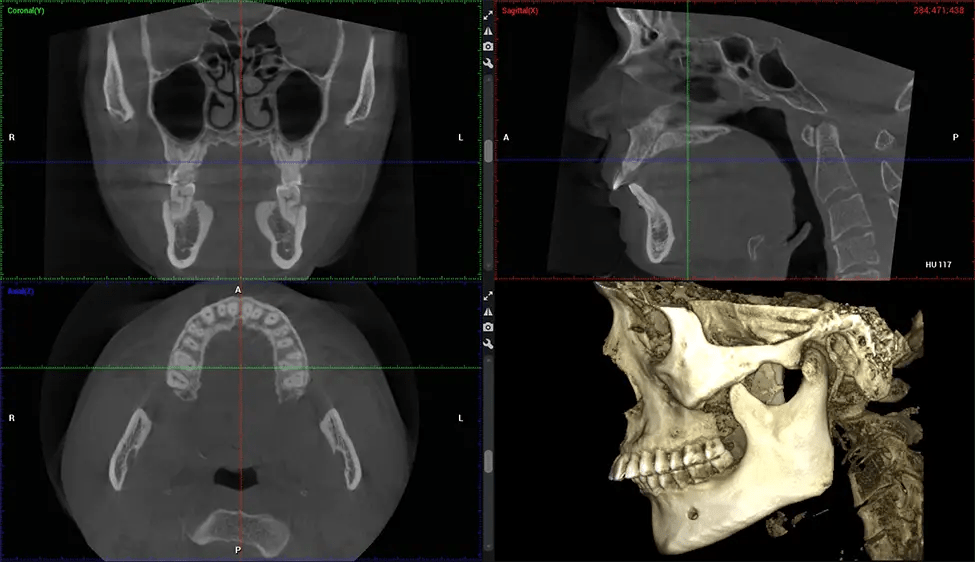

La tomografía computarizada de haz cónico (CBCT) es una técnica de imagen avanzada utilizada en odontología y cirugía maxilofacial para obtener imágenes detalladas en 3D de las estructuras orales y maxilofaciales. En Dr G Dental Studio, nuestros escáneres CBCT utilizan un haz de rayos X en forma de cono y un detector especializado para capturar imágenes desde diferentes ángulos. Luego, una computadora combina estas imágenes para crear una representación 3D de la anatomía oral del paciente.

Esta exploración 3D, llamada tomografía computarizada de haz cónico, le brinda a su dentista una imagen más completa de su anatomía bucal y sus procesos patológicos que una radiografía tradicional. A diferencia de las radiografías convencionales, que capturan una imagen 2D de la boca desde varios ángulos, una exploración 3D toma varias radiografías digitales para una imagen. Proporciona una vista completa de la mandíbula, los dientes, los nervios y los tejidos blandos. Esta vista mejorada permite a los dentistas detectar problemas menores que no son visibles en las exploraciones 2D tradicionales, como muelas del juicio impactadas o fracturas óseas en la cavidad sinusal.

Existen muchos beneficios al utilizar la tecnología CBCT, especialmente en comparación con el formato tradicional de rayos X 2D. Una de las ventajas más importantes de las exploraciones CBCT es que proporcionan mucha más información que las radiografías tradicionales. Una exploración le permite a su dentista ver imágenes desde todos los ángulos de su mandíbula y boca, incluidos los senos nasales, la cavidad nasal, los pómulos y otras áreas circundantes. Esta información adicional ayuda a su dentista a elaborar un plan de tratamiento integral que aborde todos los aspectos de su salud bucal.

Otro beneficio importante es que las imágenes 3D proporcionan imágenes más precisas de la estructura ósea. Estas imágenes son más detalladas y le brindan un diagnóstico más preciso. Un diagnóstico preciso significa un mejor tratamiento para usted.

Después del proceso de escaneo, las imágenes de rayos X capturadas son procesadas por el software CBCT, que aplica algoritmos para reconstruir una imagen 3D detallada del área escaneada. El software recopila estas imágenes de rayos X individuales y crea una representación digital en 3D de la anatomía del paciente. El dentista o el radiólogo pueden ver y analizar la imagen CBCT 3D reconstruida. Esta imagen se puede manipular, rotar y acercar o alejar para examinar estructuras específicas y evaluar la condición del paciente.